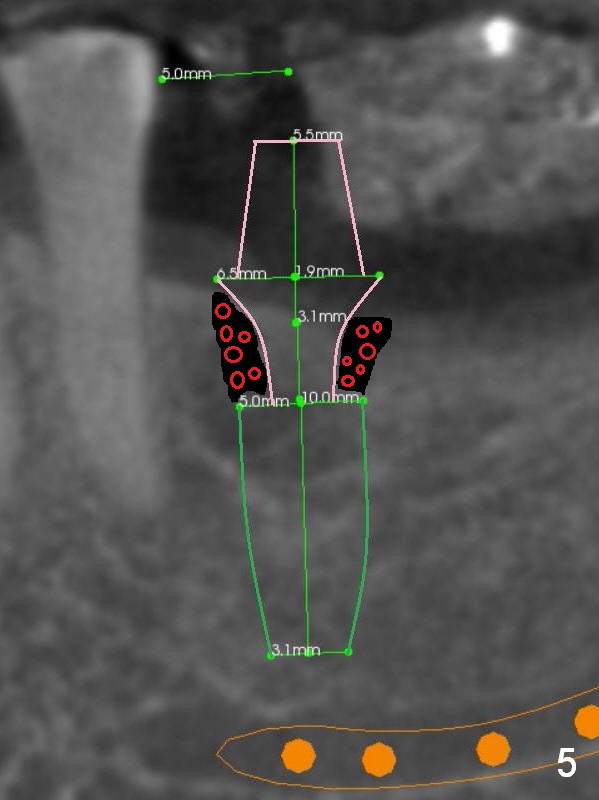

A 56-year-old man decides to have an implant at #19 after those at #13 and 14 (Fig.1 (S: CT stent)). The coronal section shows the pointed ridge (Fig.2 *). For easy implant placement and reduction in thread exposure, the ridge will be trimmed flat (Fig.3 (black area), or more exactly (funnel shaped Fig.4 (arrowheads to accommodate the shape of the cemented abutment (pink)) or concave (Fig.6)). After placing a 5x10 mm UF implant (green), bone graft to be placed (Fig.5,7 red circles) remains in place followed by collagen dressing (Fig.7 yellow lines).

Since the bone density is low (100-400 U), the last drill will be one for a 4.5 mm implant (underprep). To save the autogenous bone, reduce drill speed to 50 RPM when starting using the drill for 3.8 mm implant.